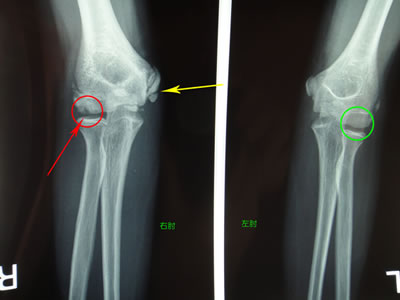

では次にレントゲン画像。(↓):向かって左側が患側(右肘)・向かって右側が健側(左肘)。

右肘外側の赤丸内矢印先に黒く映っている部分がありますが、おわかりになりますでしょうか?

左肘の緑丸内は黒い部分がありません。

離断性骨軟骨炎です。

黄色矢印先は、先述エコー像内側の黄色矢印に相当します。